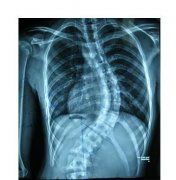

强直性脊柱炎本身是慢性的疾病,主要影响的部位是骶髂关节和脊柱这些部位,表现出来的是这些部位的疼痛和出现肿胀的状态,下面 贵阳风湿病中医院 就详细介绍一些常见的症状都有什么,以便于让大家更加全面的了解这个疾...[详细] 2025-01-24

强直性脊柱炎这个疾病应该比较熟悉,但是对它在各个阶段的会发生的病症可能不太了解,当自身出现了这样的状况时容易忽略,大家平时可以多去学习一些有关这类病的常识,这对早期发现疾病有一定的帮助。 强直性脊柱炎有什么症状 一 强直性脊柱炎早期表现 对于...[详细] 2025-01-03

让患者失去行动能力是强直性脊柱炎这个疾病在晚期的时候会造成的后果,因此发现疾病就一定要抓紧时间去治疗,不要让疾病慢慢的恶化后导致非常严重的后果之后只有无力挽回的无奈,因此期望接下来介绍的疾病的表现能够给大家一个提醒。 强直性脊柱炎会发生的...[详细] 2025-01-03